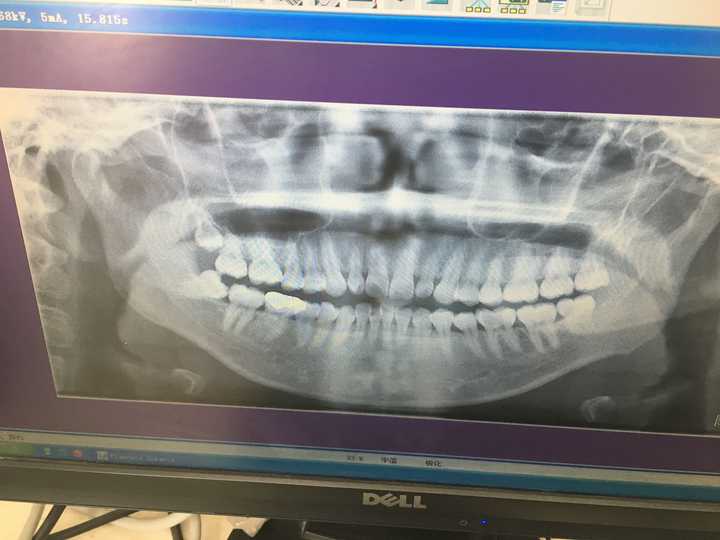

PO上一張比較有說服力的圖見識一下

沒錯!

你猜的沒錯,

那是我,美不美?(我狂笑,hahaha~)

前個星期拔了我的第三顆智齒

想到的優秀的你們

然後就留了份資料

你們想看么

智 齒

我的~~